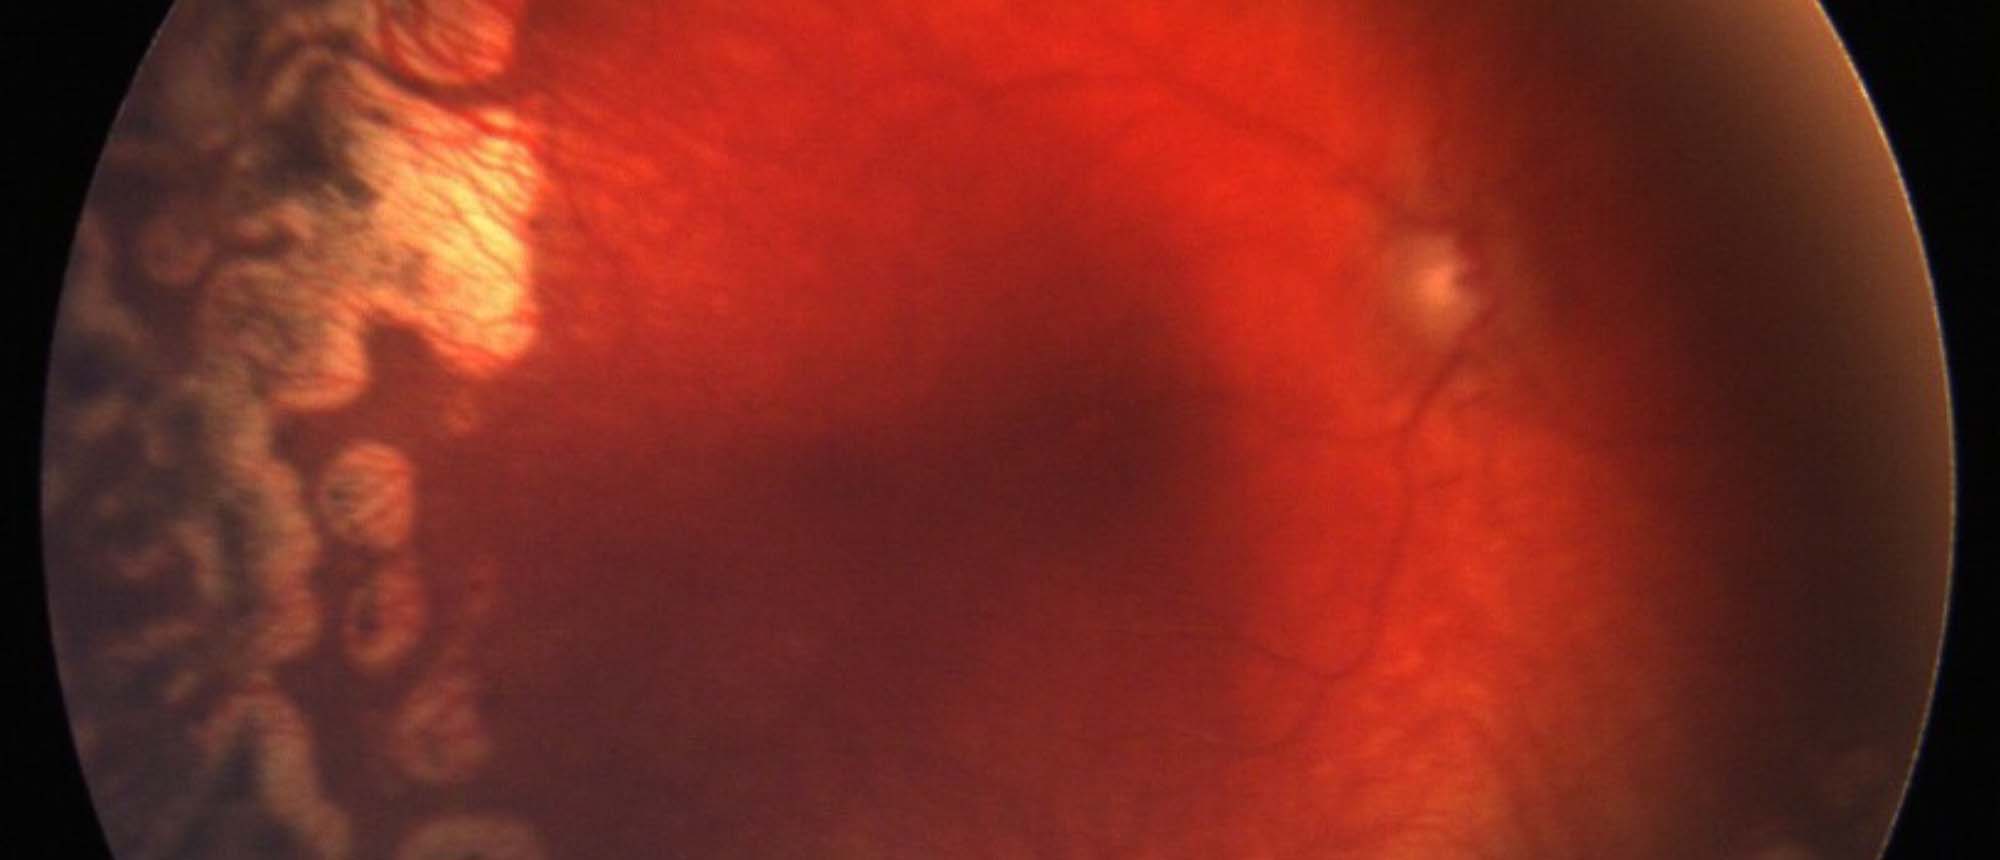

Hereditary Transthyretin Amyloidosis (hATTR) This report describes a case of hereditary transthyretin amyloidosis (hATTR) in an elderly patient who presented with bilateral retinal arteriolar vascular sheathing and vitreous hemorrhage in one eye. The patient underwent a full history, physical exam,…